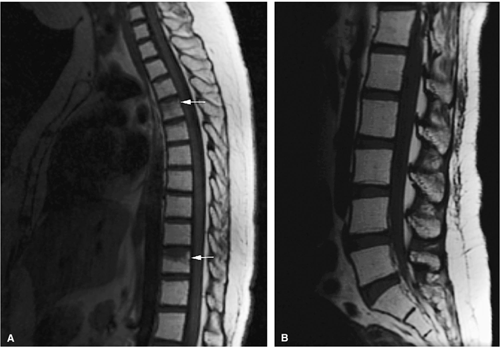

FIGURE 13.26 ● Bone marrow transplant for chronic leukemia. Hypoplastic fatty marrow demonstrates bright marrow signal intensity on sagittal T1-weighted images of the thoracic (A) and lumbar (B) spine. Compression deformities are noted in the thoracic spine (arrows).

|